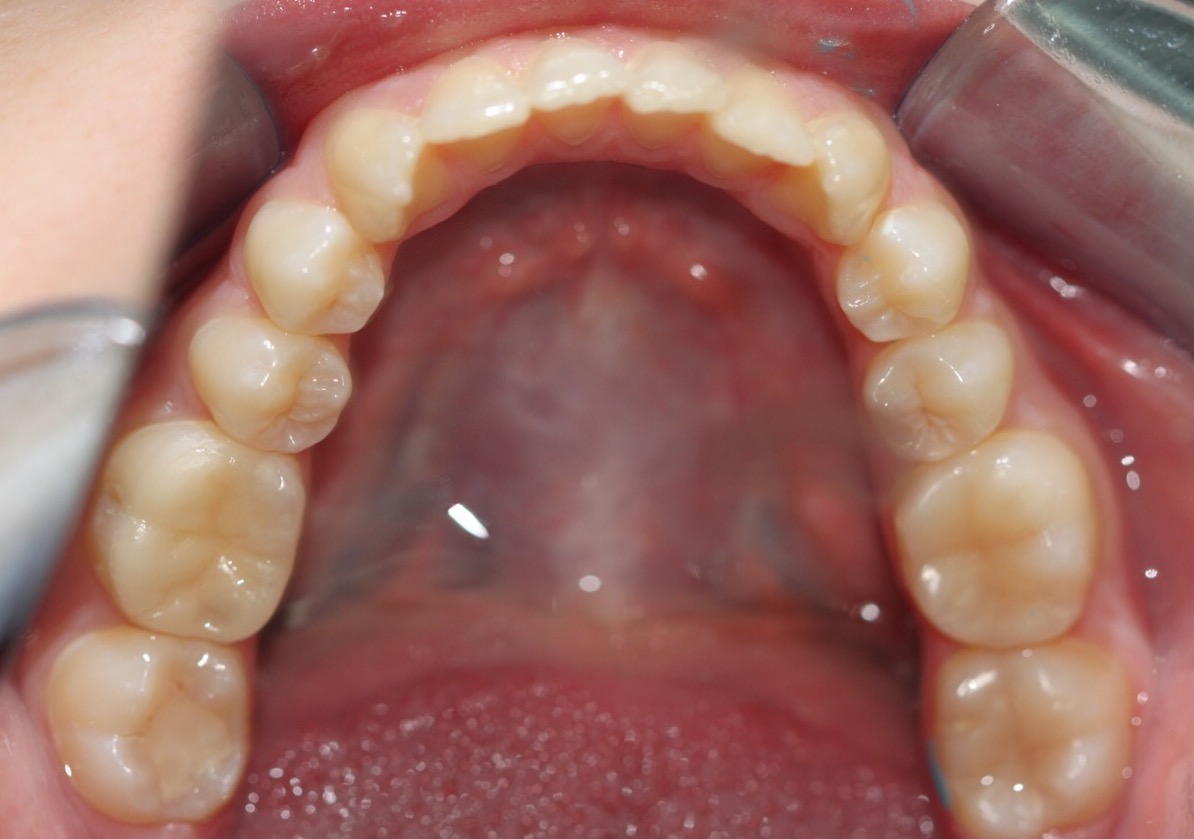

Invisalign состоит из набора индивидуальных, практически невидимых, съёмных капп(элайнеров), сменяемых 1 раз в 2 недели. Элайнеры за этот срок перемещают зубы до рассчитанного положения, после чего пациент меняет их на следующую пару.

В первый прием доктор снимает слепки с зубов пациента или делает сканирование(цифровой слепок)и отправляет их в лабораторию. Вместе со слепками или сканом доктор направляет специальную инструкцию, где подробно описывает все детали будущего лечения.

Если за зубами в брекетах требуется трудоемкий уход, без которого человеку грозит кариес и могут возникнуть проблемы с деснами, то с элайнерами режим гигиены полости рта остается стандартным. Вы просто снимаете каппы и чистите зубы как обычно.